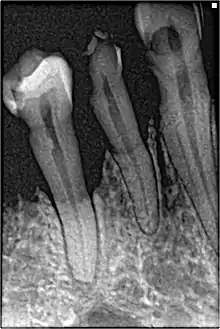

In periodontal health, the alveolar bone surrounds the teeth and forms the bony socket that supports each tooth. The buccal and lingual plates and lining of the sockets are composed of thin, yet dense compact or cortical bone.[3] Within the cortical plates and dental sockets lies cancellous bone, a spongy or trabecular-type bone which is less dense than compact bone.[6] The anatomic landmarks of the alveolar process includes the lamina dura, the alveolar crest, and the periodontal ligament space.[9]

If disease is identified through this process, then a full periodontal analysis is performed, often by dental hygienists, oral health therapists, or specialist periodontists. This involves full mouth periodontal probing and taking measurements of pocket depths, clinical attachment loss and recession. Along with this other relevant parameters such as plaque, bleeding, furcation involvement and mobility are measured to gain an overall understanding of the level of disease. Radiographs may also be performed to assess alveolar bone levels and levels of destruction.[40]

- Severity: Interdental clinical attachment level at site with greatest loss; Radiographic bone loss and tooth loss.

- Complexity of management; Probing depth, pattern of bone loss, furcation lesions, number of remaining teeth, tooth mobility, ridge defects, masticatory dysfunction.